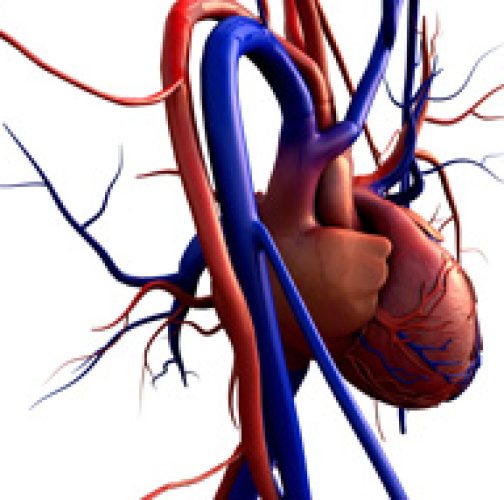

בימים חמים הלב שלנו חווה עומס יתר – כלי הדם מתרחבים, ולחץ הדם יורד. על מנת לספק את הספקת הדם הסדירה, הלב עובד במאמץ יתר. לכן, בימי הקיץ החמים, כמו אלה המתרגשים עלינו באחרונה, חשוב מאוד להקדיש תשומת לב לבריאות הלב ולמניעת מחלות הלב.

בימים חמים הלב שלנו חווה עומס יתר – כלי הדם מתרחבים, ולחץ הדם יורד. על מנת לספק את הספקת הדם הסדירה, הלב עובד במאמץ יתר. לכן, בימי הקיץ החמים, כמו אלה המתרגשים עלינו באחרונה, חשוב מאוד להקדיש תשומת לב לבריאות הלב ולמניעת מחלות הלב.

על פי הסטטיסטיקה, בשנים האחרונות, התקפי הלב הפכו "צעירים" יותר. על קבוצת הסיכון נמנים לא רק אנשים מבוגרים אלא גם גברים ונשים צעירים יותר – החל מגיל 35.

ההשפעה השלילית על עבודת הלב לא נובעת רק מהחום ומתנודות מזג האוויר אלא גם מאורח חיים לא בריא. מחסור בשעות שינה, ובפעילות גופנית, הרגלים מזיקים (עישון, אלכוהול), לחץ בעבודה, משקל יתר – כל אלה מספיקים על מנת שגם לבו של אדם בריא יחווה מאמץ יתר. אם כן, כיצד נשמור על בריאות לבנו, במיוחד בימי הקיץ הלוהטים? קבלו כמה עצות.